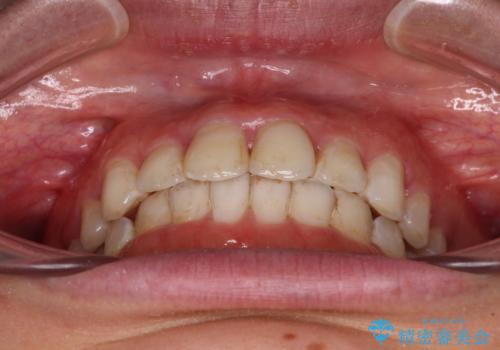

前歯の捻れを改善 インビザラインによる矯正治療

- 前歯の翼状捻転を気にして来院された患者様です。

全体的に叢生は軽度であったため、インビザラインにて矯正治療を行うこととしました。

前歯の幅の大きさも気になっていたため、IPRにより叢生を解消するとともに、歯の大きさも改善しました。